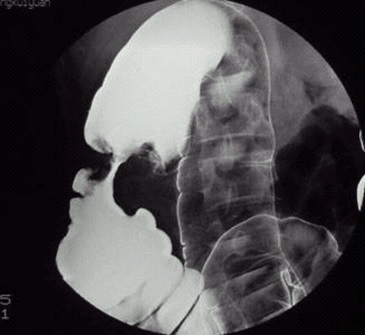

05卷-3.病史:女性,52歲,觸及腹部包塊3周。診斷(本題滿分2.00分)

本題答案:B

題目解析:【該題針對“造影-結腸癌”知識點進行考核】